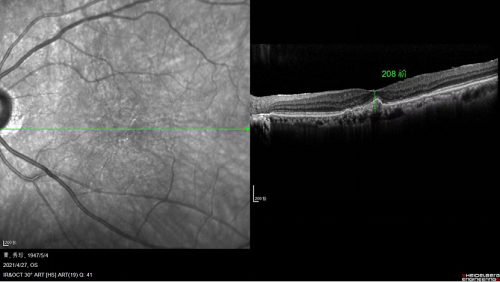

注藥手術(shù)前,黃斑水腫嚴重

完成一個療程(三針)治療后

黃斑水腫消退,黃斑厚度大大降低